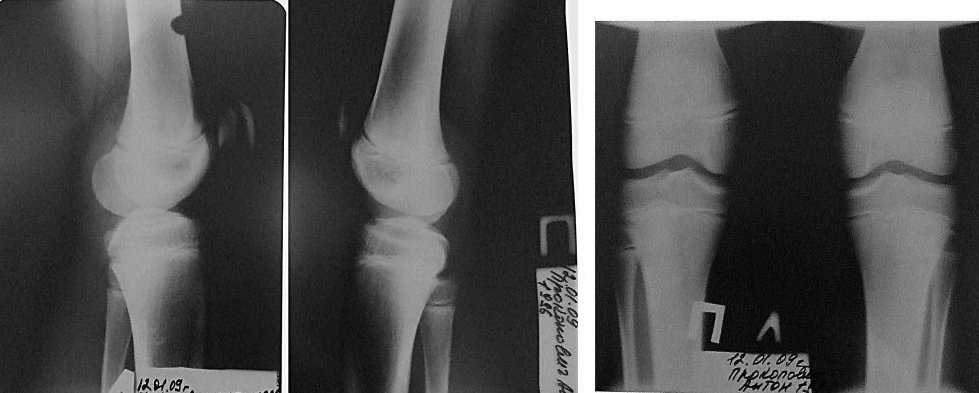

Мальчик занимается спортом - баскетбол с шести лет вместе с братом (двойняшки). До прошлого лета никаких проблем не было. Но после приезда из спортлагеря и простудной болезни стали болеть колени. У брата (если эта информация важна ни тогда, ни сейчас никаких проблем нет, нагрузки на тренировках получали одинаково). После двух месяцев боли правого колена (боль появляется при нагрузках - в основном при резком беге, ускорениях, а также при сгибании и разгибании колена в крайние положения) мы сдали анализ на ревматоидный артрит (анализ отрицательный), снимки колена и показали спортивному врачу. Диагноз был поставлен, что это у мальчика болят шляттеры. На два месяца он прекратил тренировки и упражнениями тренировал (закачивал) правую (и заодно левую ногу). Однако к новому году тенденция поменялась, правое колено стало проходить, а левое наоборот беспокоит, за это время боли так и не ушли. Мальчик начал тренировки (по возможности) в зале. К весне правое колено перестало болеть полностью но стало очень сильно болеть левое. После одного из турниров к боли добавился отек (колено довольно сильно опухло) и болело не позволяя делать активные физические упражнения и нагрузки. Нами были сделаны повторно снимки обеих колен (прикреплены). Все это время (уже 9 месяцев) постоянно мажем коленные суставы вольтареном. Хочется попросить у вас профессиональной помощи и по возможности (если сталкивались с подобными ситуациями) порекомендовать наши действия и какой можно поставить диагноз.Заранее спасибо всем за ответы и советы!

По снимкам (мелким, правда) ничего тревожного не видно. Описанное вполне укладывается в уже поставленный диагноз болезни Осгуда-Шлаттера . Это хорошо знакомая всем проблема, никаких откровений искать не надо. Местные врачи вполне способны сами разобраться.